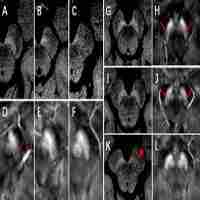

Nigrosome Imaging and Neuromelanin Sensitive MRI in Diagnostic Evaluation of Parkinsonism